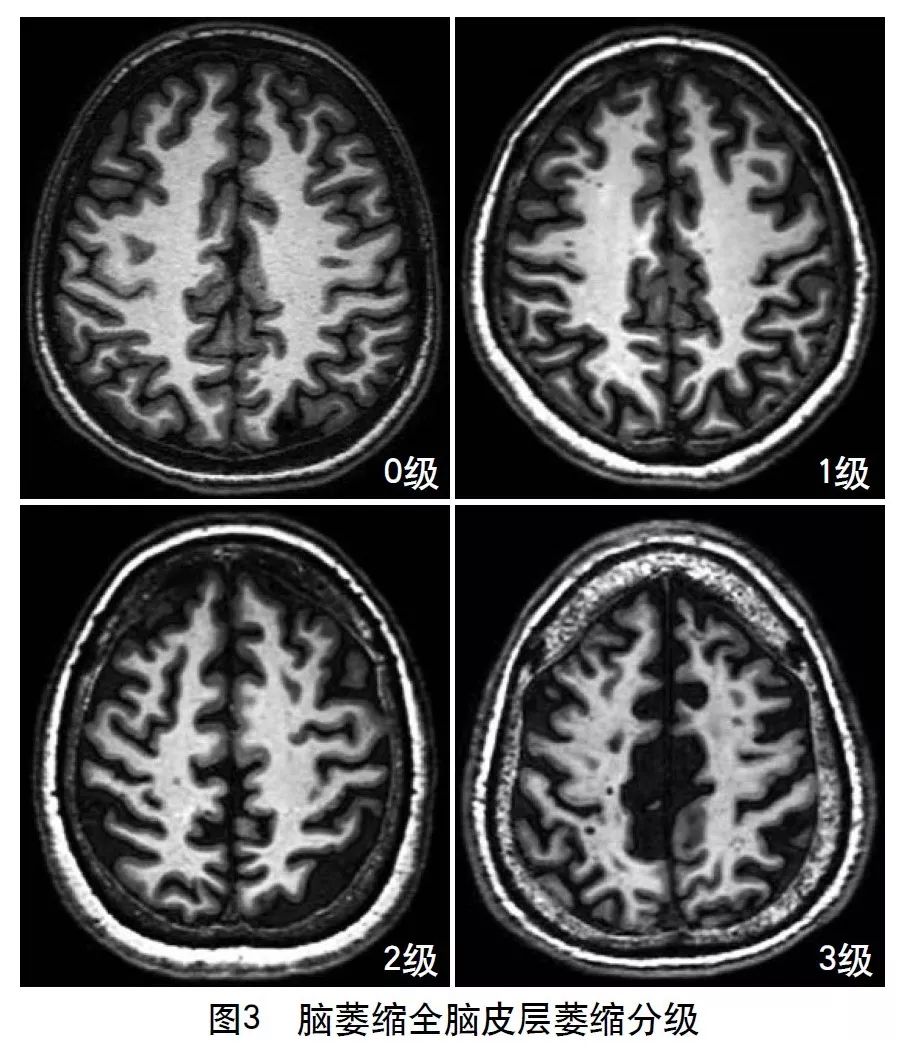

4.2.6 脑萎缩

2013年的共识指南将脑萎缩定义为与特定的局灶性损伤,如脑外伤或脑梗死无关的脑容积减少。脑萎缩可以是广泛的或局部的(如特定的脑叶或海马等特定区域),可以是对称或不对称的,亦可以是组织选择性的(如发生在白质等某一特定组织层)。目前不同部位的脑萎缩有相应的诊断标准,全脑皮层萎缩分级用于评价全脑(图3);内侧颞叶萎缩分级主要评价颞叶内侧,重点是海马(图4);Koedam分级主要评价顶叶,尤其是扣带回和楔前叶(图5);Kipps/Davies分级主要评价额颞叶(图6)。推测脑组织减少是由脑沟(周围)和脑室(中心)的脑脊液空间相对于颅内容积扩大所引起的。